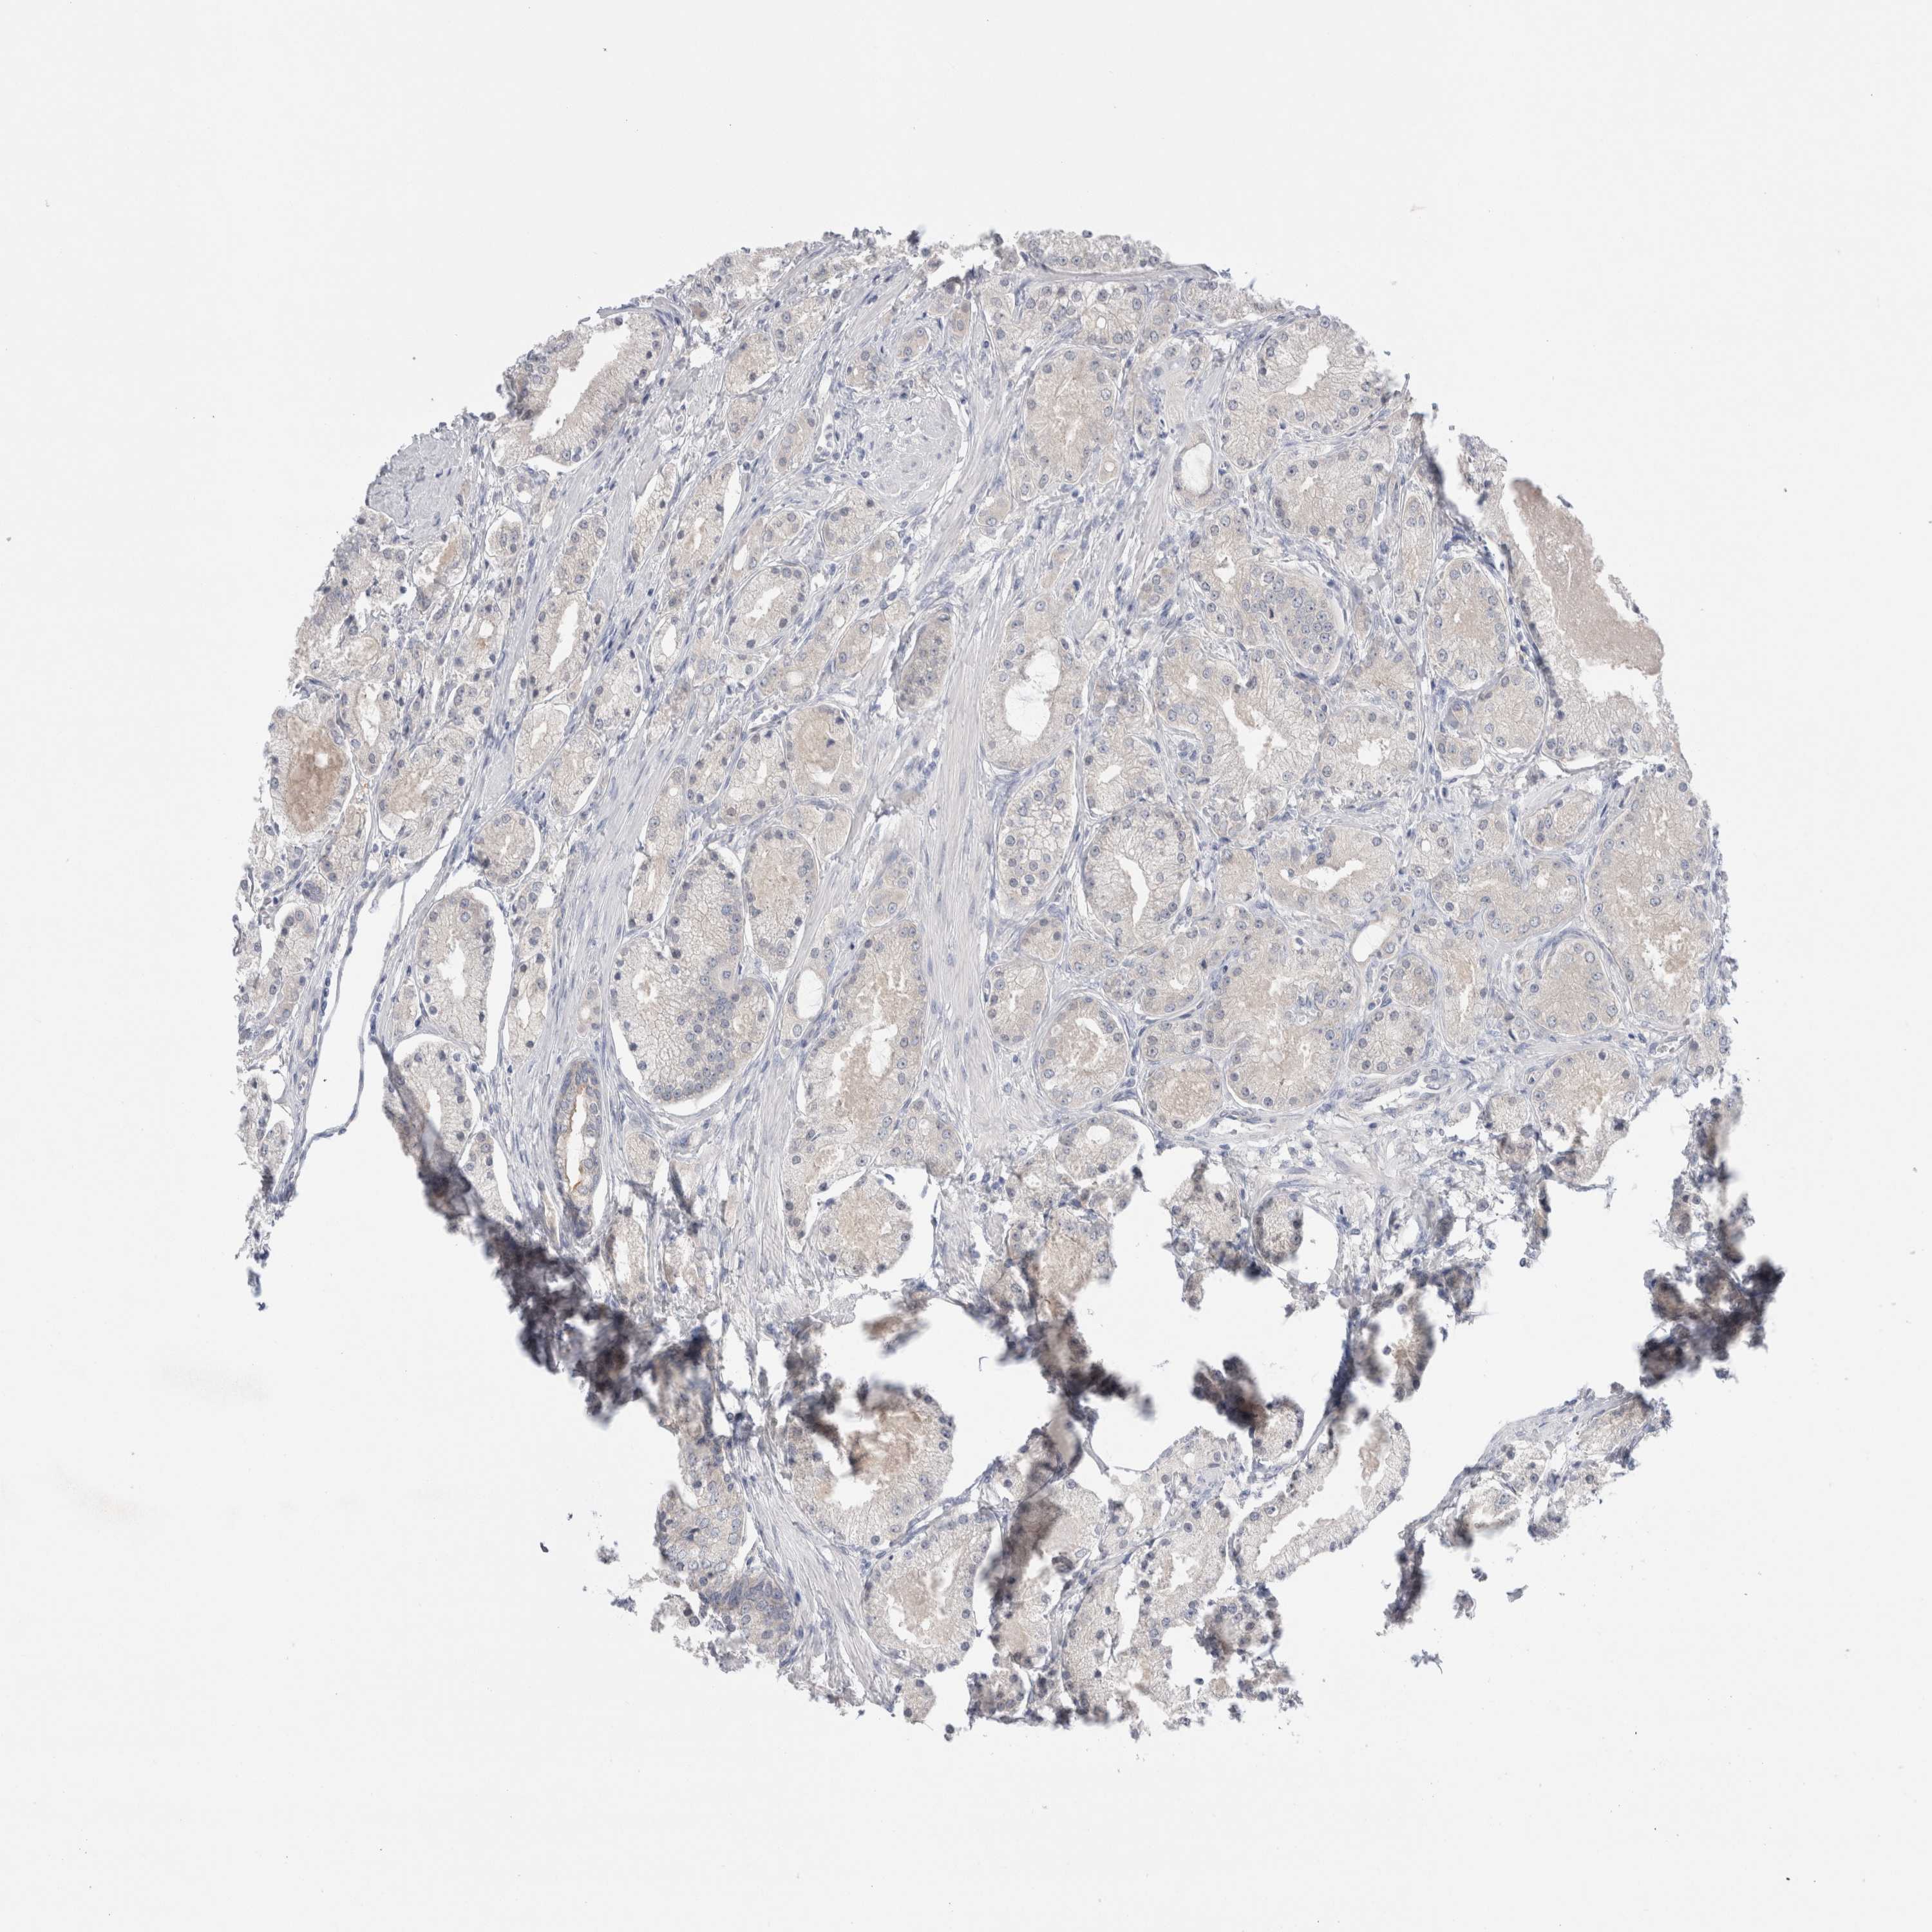

PROSTATE CANCER - Protein expressioni

A mouse-over function shows sample information and annotation data. Click on an image to view it in a full screen mode. Samples can be filtered based on level of antibody staining by selecting one or several of the following categories: high, medium, low and not detected. The assay and annotation is described here.

Antibody stainingi

Antibody staining in the annotated cell types in the current human tissue is reported as not detected, low, medium, or high, based on conventional immunohistochemistry profiling in selected tissues. This score is based on the combination of the staining intensity and fraction of stained cells.

Each image is clickable and will lead to virtual microscopy that enables deeper exploration of all samples and also displays staining intensity scores, fraction scores and subcellular localization as well as patient and tissue information for each sample.

Antibody HPA024000

Antibody HPA024001

Antibody HPA024467

Staining

High

Medium

Low

Not detected

Intensity

Strong

Moderate

Weak

Negative

Quantity

>75%

75%-25%

<25%

None

Location

Nuclear

Cytoplasmic/membranous

Cytoplasmic/membranous,nuclear

Adenocarcinoma, High grade

Adenocarcinoma, Low grade